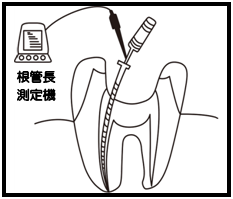

Q1.痛みはありますか? ② 次に、「根管長測定器」という機械を使い、根っこの長さを正確に測ります。

② 次に、「根管長測定器」という機械を使い、根っこの長さを正確に測ります。